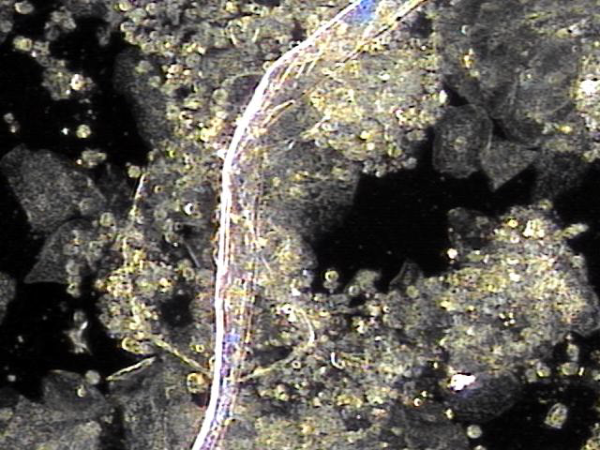

주 2회 전립선의 표적 치료중 전립선액과 정낭액 그리고 전립선 결석과 정관등에 침범하여 퍼지고 있는 균의 배양과 항생제 민감도 검사를 하기위해 표적 치료후 배출된 전립선액의 현미경 검사 자료입니다.

탈락된 상피세포 덩어리와 혈정액과 전립선 결석과 전립선암의 전암병변 의심되는 자료입니다.

This is a microscopic examination of prostatic fluid discharged during biweekly targeted prostate therapy. The sample was obtained to conduct bacterial culture and antibiotic sensitivity testing for organisms invading and spreading through the prostatic fluid, seminal vesicle fluid, prostate calculi, and vas deferens. The findings include clusters of desquamated epithelial cells, hematospermia, prostatic calculi, and features suspicious for precancerous lesions of prostate cancer.